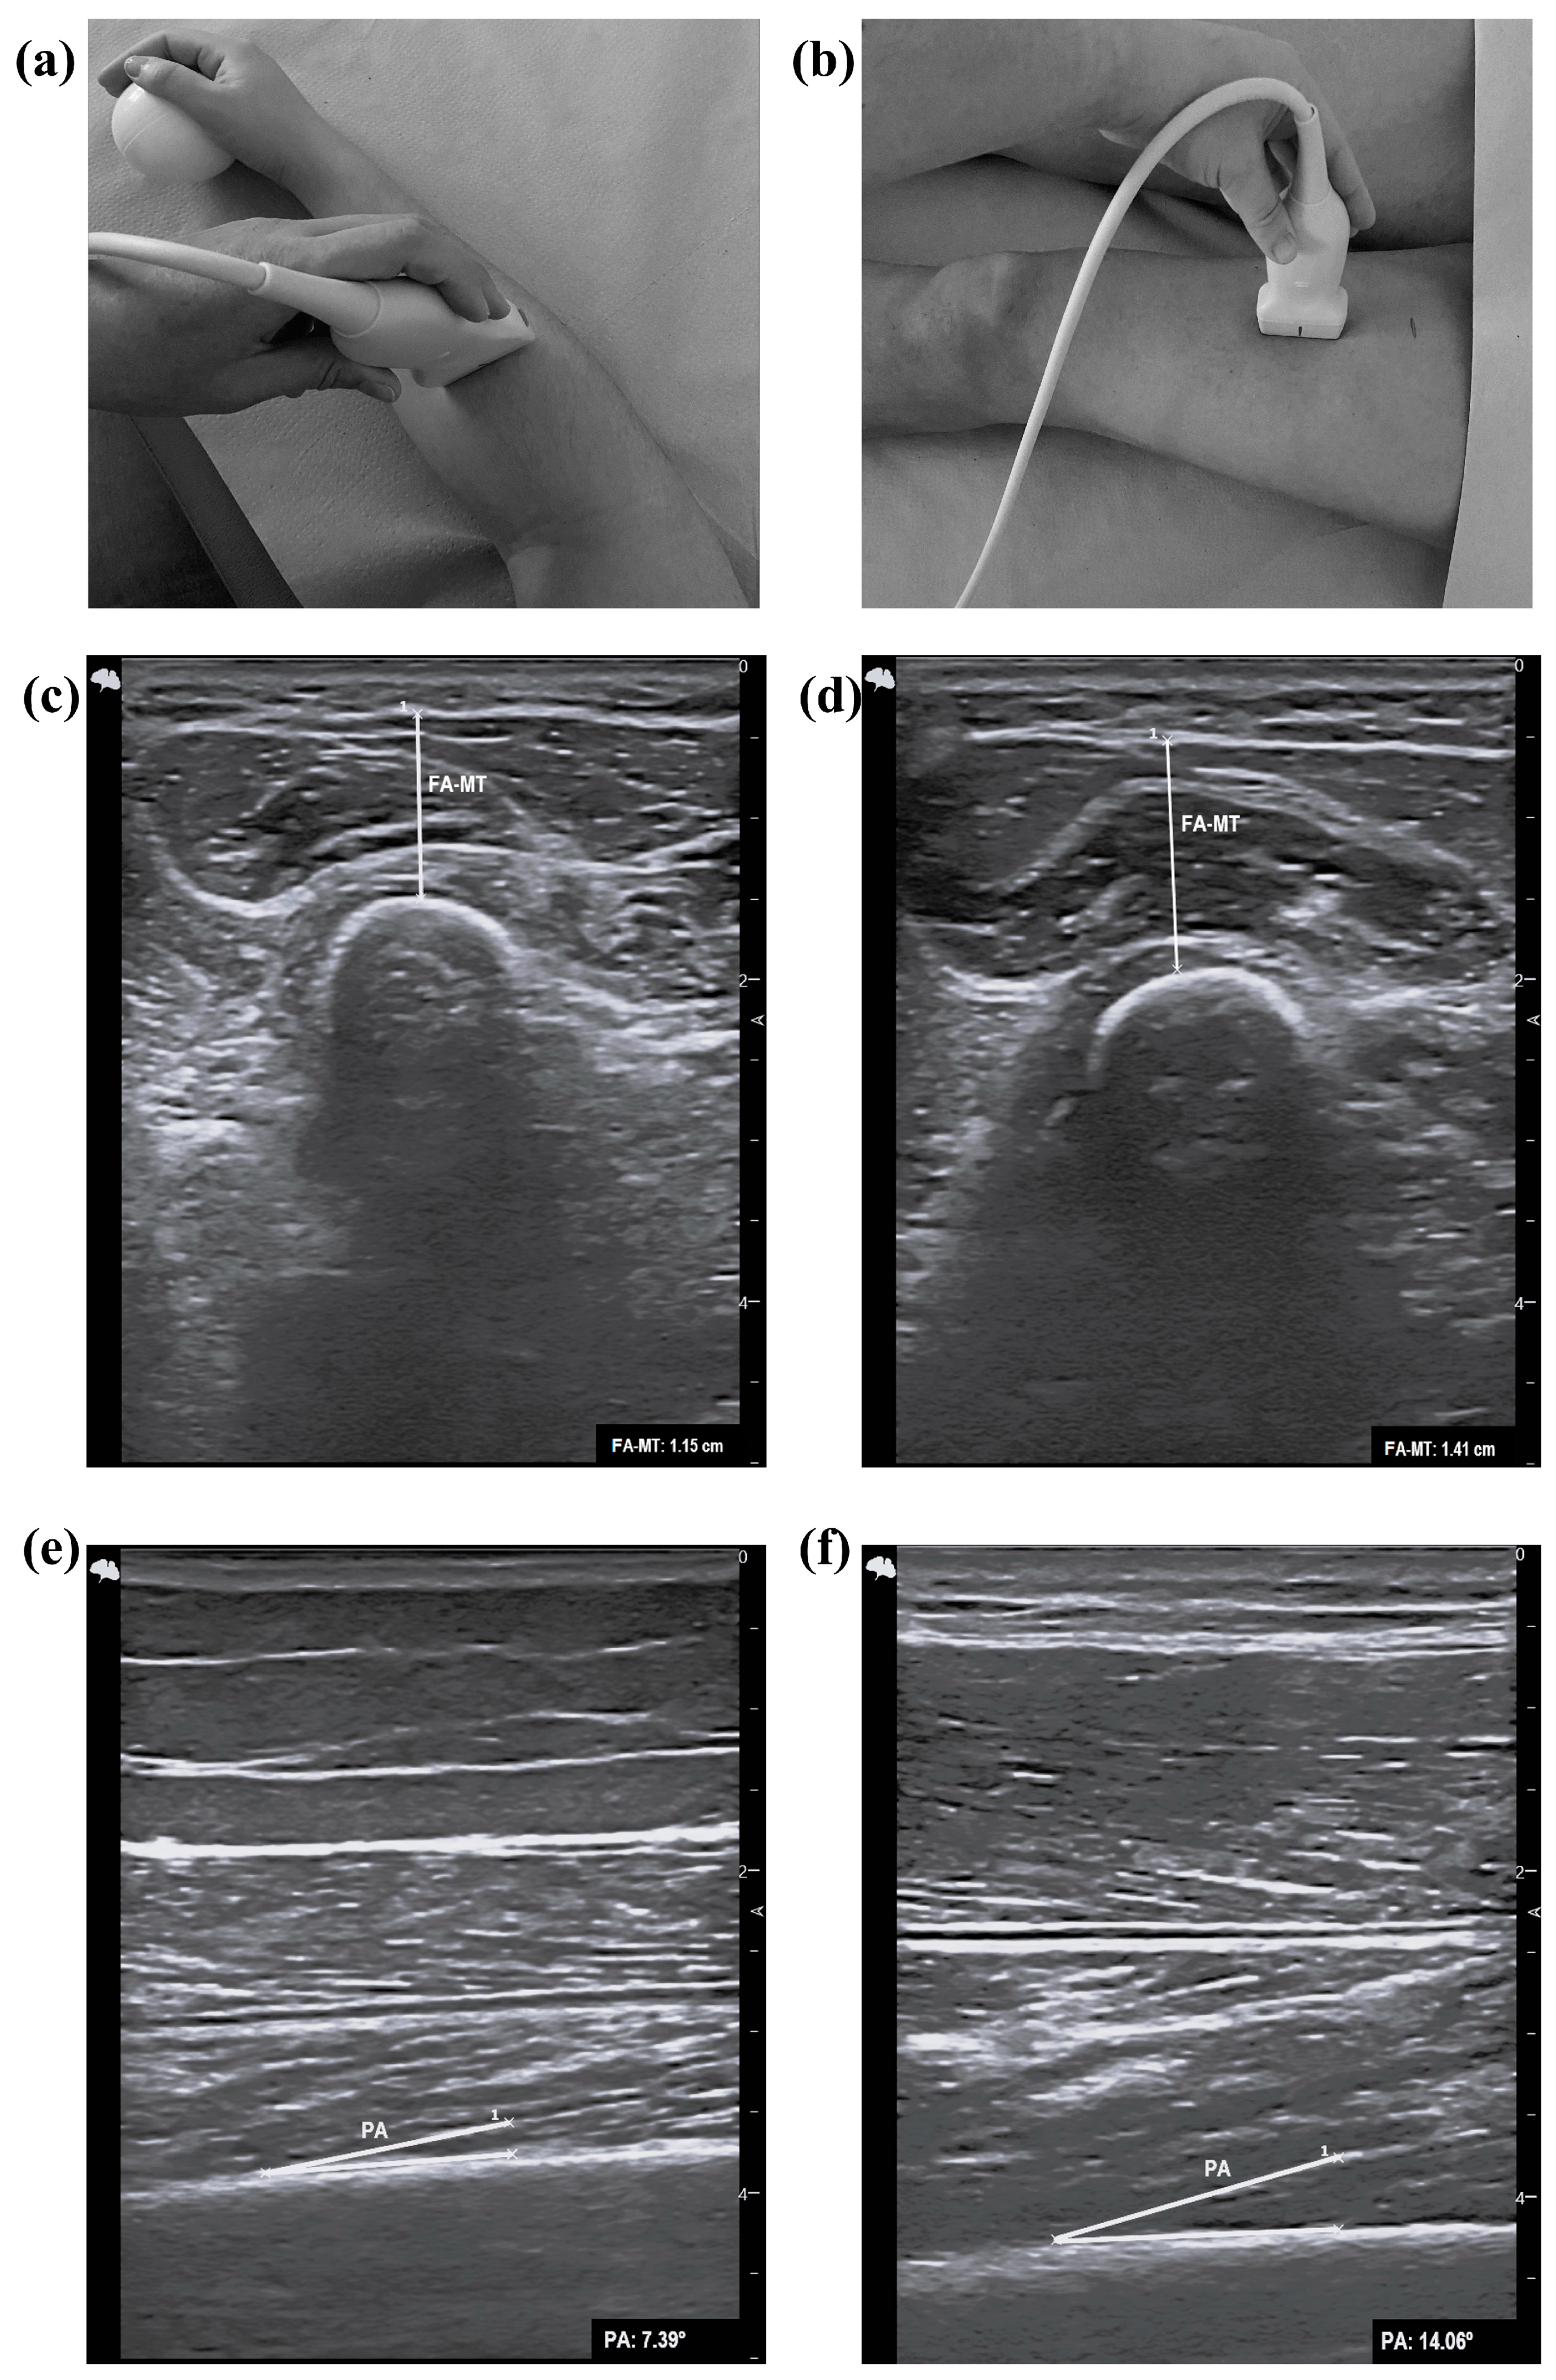

2.5. Assessment of Ultrasound Parameters

- Meza-Valderrama, D.; Sánchez- Rodríguez, D.; Perkisas, S.; Duran, X.; Bastijns, S.; Dávalos-Yerovi, V.; Da Costa, E.; Marco, E. The Feasibility and Reliability of Measuring Forearm Muscle Thickness by Ultrasound in a Geriatric Inpatient Setting: A Cross-Sectional Pilot Study. BMC Geriatr. 2022, 22, 137. [Google Scholar] [CrossRef]

| Forearm | ||||||

| FA-MT (cm) | All | 1.02 ± 0.33 | 1.48 ± 0.40 | 0.001 | <0.001 | 0.184 |

| Men | 1.36 ± 0.30 | 1.69 ± 0.33 | 0.064 | |||

| Women | 0.94 ± 0.29 | 1.17 ± 0.27 | 0.137 | |||

| Upper leg | ||||||

| PA (°) | All | 9.63 ± 3.32 | 10.56 ± 2.26 | 0.317 | 0.597 | 0.403 |

| Men | 8.14 ± 3.20 | 11.40 ± 2.52 | 0.085 | |||

| Women | 9.98 ± 3.30 | 9.38 ± 1.21 | 0.741 | |||

| Upper leg PA (°) | |||||||

| Men | 0.776 | 0.515–1.036 | 0.038 | 0.857 | 0.286 | 0.571 | 10.11 |

| Women | 0.453 | 0.259–0.648 | 0.639 | - | - | - | - |

| Men | 0.796 | 0.554–1.038 | 0.017 | 0.714 | 0.143 | 0.571 | 1.41 |

| Women | 0.710 | 0.509–0.910 | 0.041 | 0.516 | 0.000 | 0.516 | 0.94 |